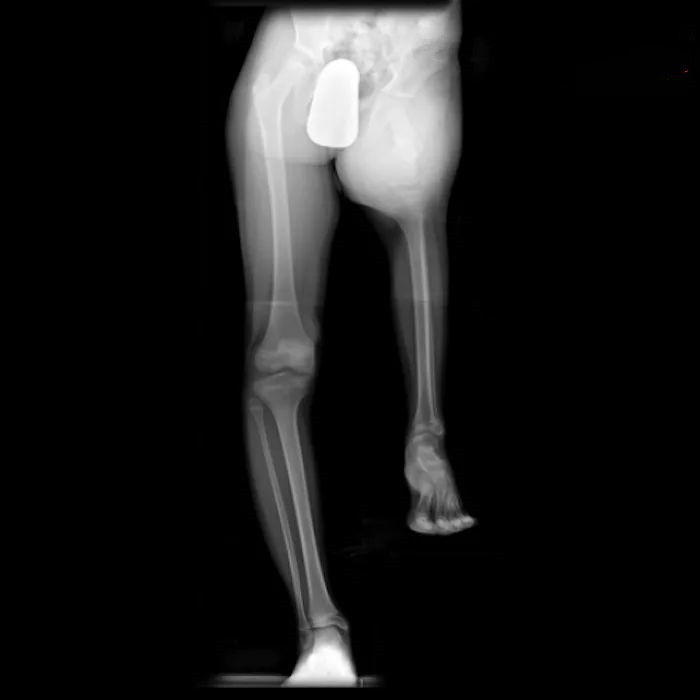

这一名病人直肠内有一个茄子?!医生也不知道她是怎么塞进去的。